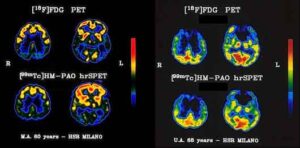

CRI